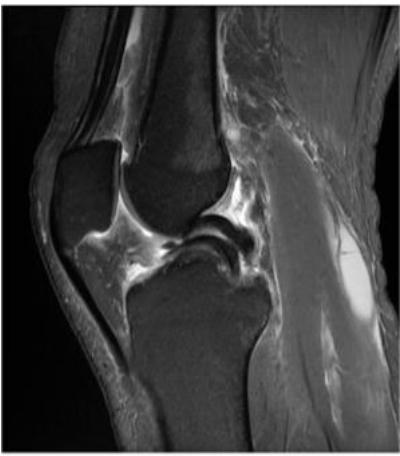

What is the imaging modality and diagnosis?

- Modality: MRI

- Diagnosis: ACL tear

What finding is shown in this MRI?

-

Torn ACL